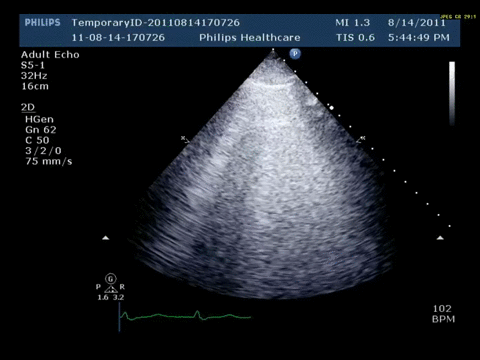

Bedside Lung Ultrasonography: Using either a low-frequency phased-array probe or a high-frequency linear probe, the following finding is present bilaterally on atleast two locationas on each side.

Based on his history and lung ultrasound findings, which one of the following is likely to explain his dyspnea?